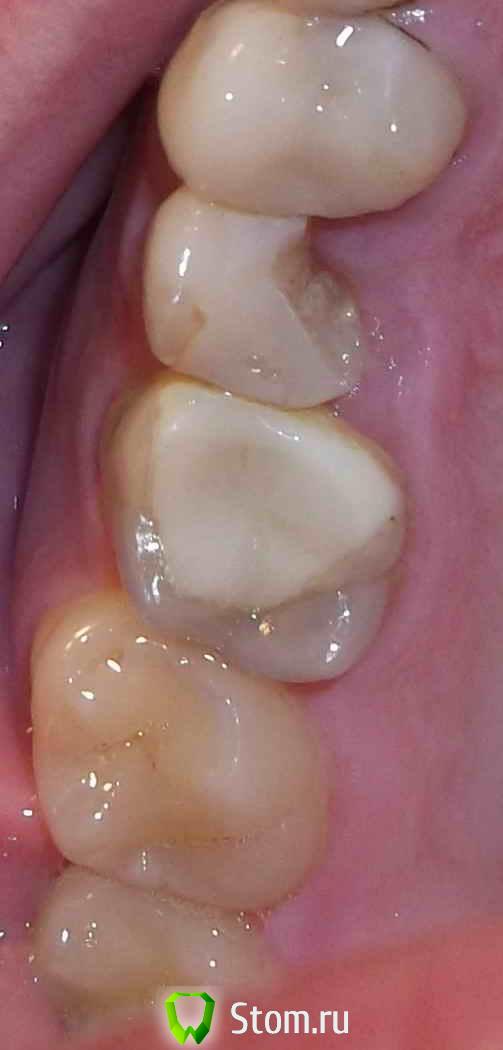

Constantin Опубликовано 30 марта, 2012 Поделиться Опубликовано 30 марта, 2012 Здравствуйте.Нужна консультация по следующему вопросу.Скололась часть пломбы на верхней 5-ке справа.В своё время у этого зуба откололась стенка, скол был под десну.Тогда зуб мне восстановили пломбой и стекловолоконным штифтом.В нынешней ситуации пломбу уже ставить не хотят и отправляют к ортопеду.Был на консультациях в разных клиниках и мнения ортопедов разделились.Первый советует что лучше уже ничего с этм зубом не делать так он дольше прослужит.Второй советует попоробовать поставить пломбу или удалить т.к. коронку ставить не на что,а вкладка в 5-ке плохо держится поэтому он этим заниматься не будет.Третий врач говорит что поскольку в одном канале штифт который вынуть не удасться можно безпроблем поставим вкладку во второй канал и установить коронку. Что посоветуете уважаемые доктора? Спасибо. Ссылка на комментарий

dok1 Опубликовано 1 апреля, 2012 Поделиться Опубликовано 1 апреля, 2012 На пальцах: что бы что-то приклеить к зубу(пломбу, вкладку, коронку), нужен хороший доступ, обзор и изоляция от влаги(слюны, крови).Ну и соответствующая плотность(прочность) ткани самого зуба.В вашем случае дефект ниже уровня десны, а это:влага, плхой обзор и неизвесная глубина распространения размягчённых поражённых тканей зуба.Простейшая механика: что бы что-то на чём-то держалось нужно хорошее основание, которое можно "зашкурить", "обезжирить" и "загрунтовать".Делайте выводы.А извлечение стекловолоконного штифта - это такая мелочь... Ссылка на комментарий